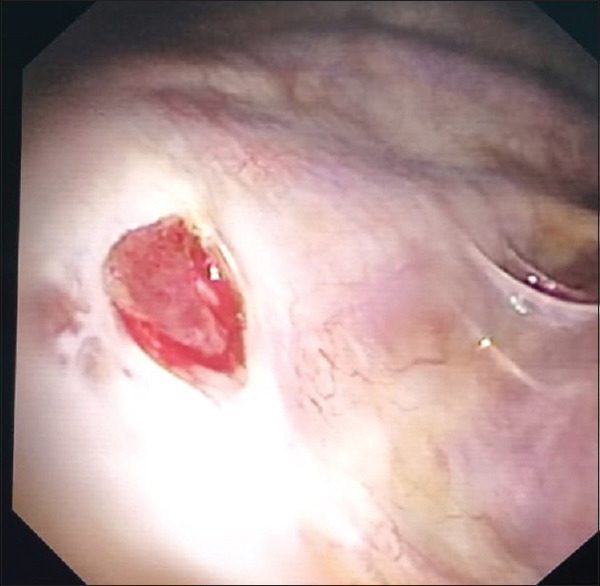

Abstract: Endometriosis is an ectopic implantation of uterine tissue and can affect the thoracic cavity, resulting in Thoracic Endometriosis Syndrome (TES). TES is rare and presents with catamenial pneumothorax, haemothorax, and hemoptysis, often coinciding with menstruation. We report a case of a 46-year-old female with a decade-long history of hemoptysis and periodic chest pain associated with her menstrual cycle. High-resolution CT scans revealed persistent pneumothorax and pleural nodules. A dry thoracoscopy was performed, and biopsies confirmed the diagnosis of TES through histopathology and immunohistochemistry. This case highlights the importance of considering TES in women with cyclic respiratory symptoms and demonstrates the diagnostic value of dry thoracoscopy in benign conditions of the pleura. Raising awareness among clinicians is crucial for timely diagnosis and management of TES, reducing patient morbidity.

Abstract Image